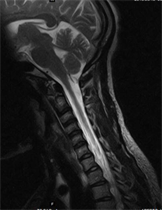

Figure 3. T2W Sag image of normal cervical spine.

Hyposignal of intervertebral disc in degenerative disc disease on T2 weighted images is the witness of the dehydration of the disc but can also translate the production sometimes anarchic collagen fibers [14]. Morphological modifications of discs are responsible of almost all root conflicts [22].